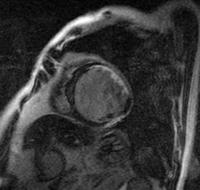

心臓MRI

MRI(磁気共鳴画像診断法:Magnetic Resonance Imaging)は、強力な磁石と電磁波を用いて、身体各所の断層像を観察できる検査です。

心筋の壁運動の評価や心筋の繊維化(ダメージを受けた部位)の評価を行います。